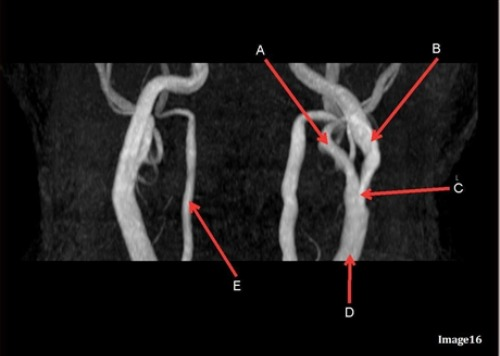

Letter A in Image 16 is responsible for blood supply to the:

C. Face

Image 16 is an example of what type of MR image?

D. MRA extracranial circulation

Letter E in Image 16 is responsible for blood supply to the:

B. Posterior brain

Letter B in Image 16 is responsible for blood supply to the:

A. Anterior brain

Letter A in Image 16 is pointing to:

B. External carotid artery

Letter B in Image 16 is pointing to:

A. Internal carotid artery

Letter C in Image 16 is pointing to:

D. Common carotid artery

Letter E in Image 16 is pointing to:

C. Vertebral artery

Letter D in Image 16 is pointing to: